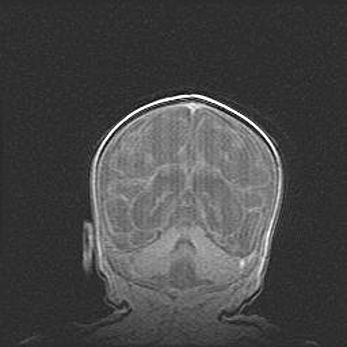

Множественные кисты обоих полушарий головного мозга, наибольшая из них в правой затылочной области. Ассиметричная атрофическая гидроцефалия.

Возраст: 7 месяцев

Вес: 5660 г

Пол: мужской

Окружность головы: 41,5 см

Срок гестации: 28-29 недель

Кисты головного мозга развиваются в результате многоочаговых некрозов вещества мозга и возникают вследствие перенесенной перинатальной инфекции, менингитов, энцефалитов, асфиксии, родовой травмы, расстройств мозгового кровообращения различного генеза. Образованию кист в веществе головного мозга плодов и новорожденных способствуют такие факторы, как высокое содержание в нем воды, недостаточная (или отсутствие) миелинизация и слабая астроглиальная реакция на повреждение.

Кисты могут сочетаться с гидроцефалией и другими поражениями головного мозга.